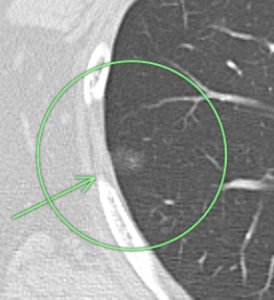

(症例2)63歳 男性

右上葉 左下葉

右上葉、○枠、矢印の部位に6.9㎜大の結節(すりガラス型)、

左下葉、○枠、矢印の部位に5.6㎜大の結節(すりガラス型)を認めました。

9年の経過で右上葉の結節は6.9㎜から9.1㎜大に、左下葉の結節は5.6㎜から6.3㎜大に増大したため、期間を開けて2回胸腔鏡下肺部分切除が行われました。

結果は両方とも早期肺がん(上皮内癌)であり、これで完治したと考えられます。

この人の場合、他の部位にもより小さなすりガラス型結節がみられ、経過観察中です。

このようにすりガラス型結節は多発することもあります。